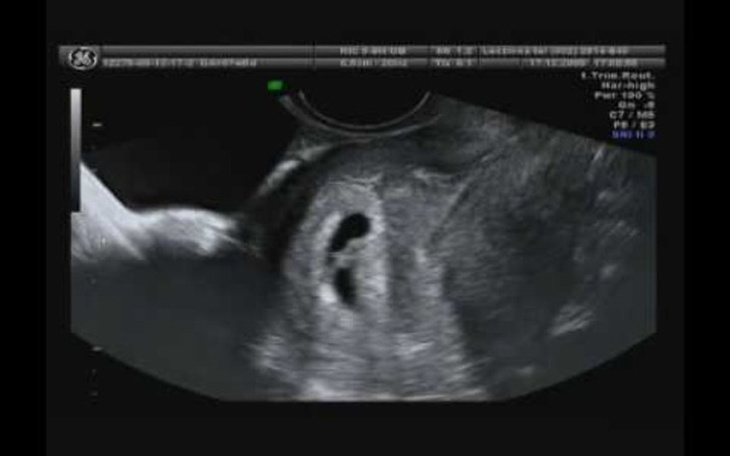

Mam na imie ola mam 35lat i nie mogę zajść w ciąże z mężem staramy się już prawie 10 lat i nic z tego i chcemy spróbować. Metodą sztucznym zapłodnieniem mamy duże nadzieje to nam się uda i tak bardzo bardzo pragniemy mieć dziecko już nie wiemy co mamy robic chyba każda kobieta pragnie mieć dziecko